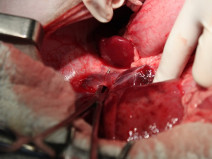

Urgence et RéanimationBourgogne Franche-Comté, G.E.U.R.154Les shunts porto-systémiques

Fort du grand succès de la journée spécialisée sur les calculs urétraux chez le chat de l’année dernière, le GEC organise le jeudi 26 Janvier 2017 une journée spécialisée autour des shunts port-systémiques.

Comme l’année dernière, cette journée destinée à des chirurgiens expérimentés, aura lieu chez le laboratoire Boehringer à Paris. L’objet n’est pas de faire le point des connaissances...